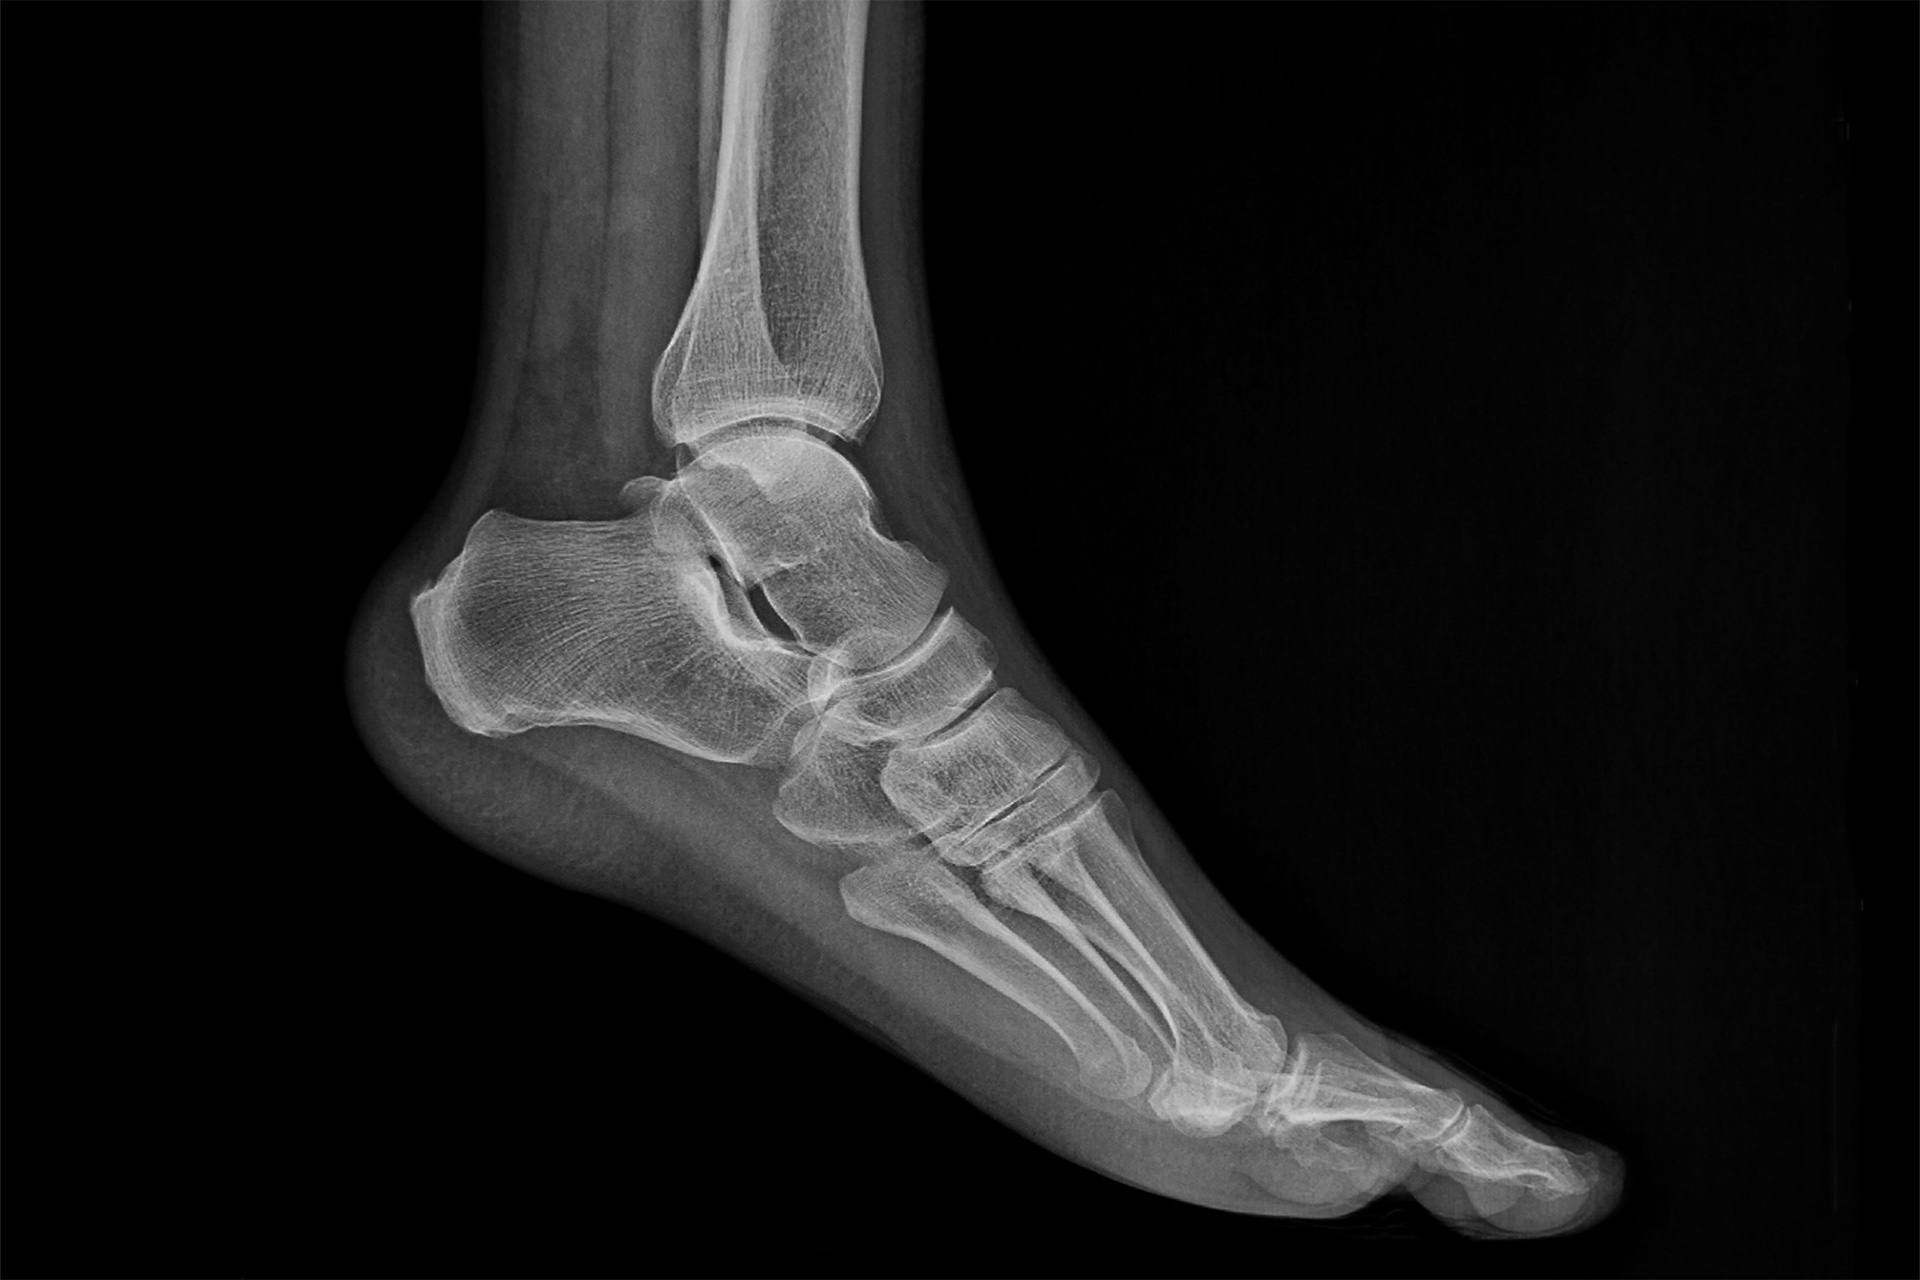

At The Foot Practice, we often use RehaWalk® pressure-sensor treadmill gait analysis to quantify how forces are distributed through the foot and where the Achilles tendon works hardest, which helps tailor loading changes. Imaging is reserved for persistent or complex cases. Ultrasounds can show tendon thickening and calcific changes; X-rays reveal bone spurs; and magnetic resonance imaging is helpful when a partial tear is suspected.

Bone spurs, or bony growths that develop on the heel bone, are common in insertional Achilles tendinopathy. These bone spurs can rub against the Achilles tendon where it inserts into the heel, causing increased irritation, inflammation and tendon pain. It’s important to understand that not every bone spur causes symptoms. Some people may have bone spurs without any Achilles tendon pain.